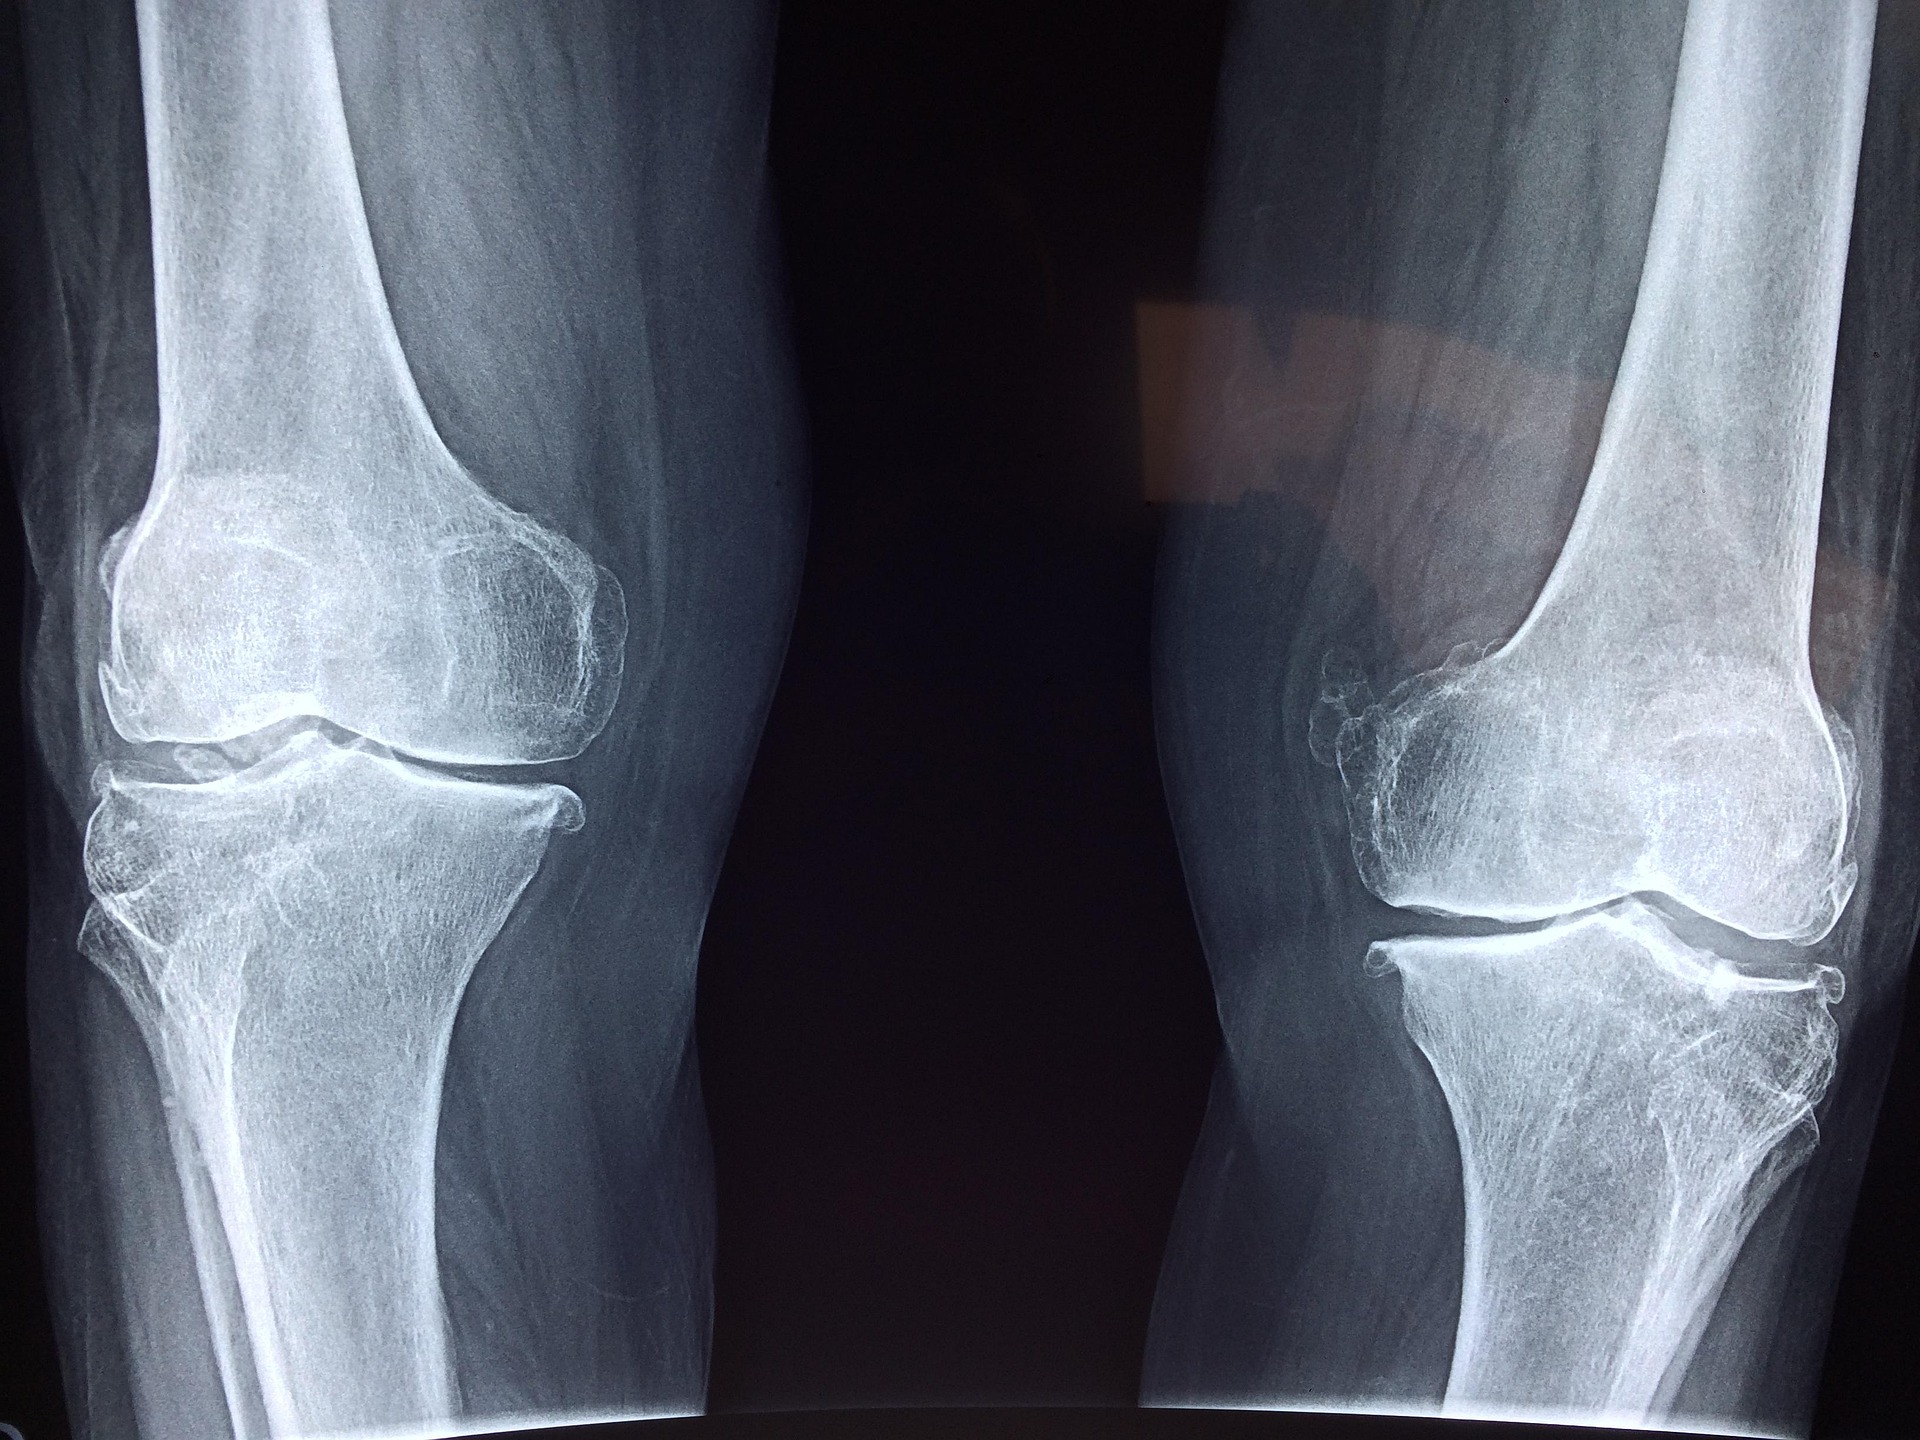

With an ageing population, sport injuries and obesity among the causes, the rate of joint replacement surgery is increasing at a rapid rate. Currently more than 85,000 hip and knee replacements are undertaken each year in Australia. The outcomes of joint replacement are variable.